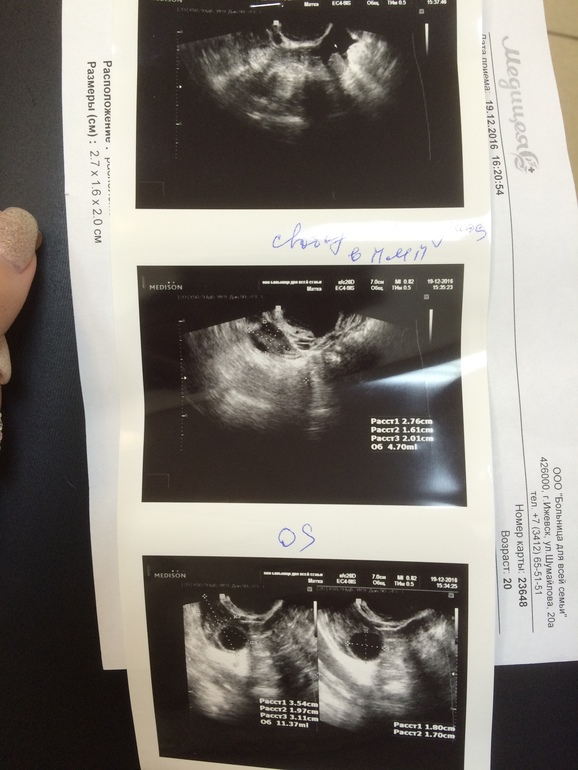

ФолликулометрияСходила вчера, 24.12.на 20 д.ц.на фолликулометрию. Овуляция по тестам и по ЯБ была примерно в среду утром (17 д.ц.), но на фолликулометрии сказали, что О уже не будет, т.к.фоллик перерос в кисту 32х25 мм, а эндометрий уже секреторный, т.е.соответствует 2й фазе. Но она так сомневалась, когда делала узи, с сомнением в голосе все говорила. Она распечатала мне фото, я посмотрела, и мне кажется, что на фоллик не похоже, края неровные, и больше похоже на кисту ЖТ, плюс жидкость в брюшной полости...А это значит, что овуляция была. Но расстраивает, что образование аваскулярное, т.е., отсутствует кровоток(( фото узи ниже.